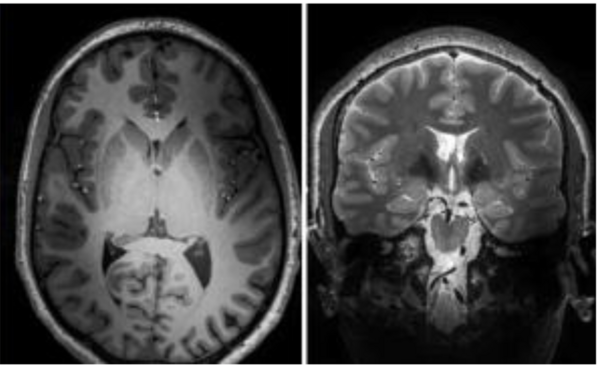

Kursen anordnas av Humanistlaboratoriet & Lund University Bioimaging Center (LBIC) och utgör en introduktion till strukturell och funktionell hjärnavbildning med magnetisk resonanstomografi (MRI) för användare utan bakgrund inom fältet. Syftet med kursen är att lära deltagarna grunderna i MRI. Kursen introducerar fMRI (funktionell MRI), dMRI (diffusions MR) och sMRI (strukturell MR) ur ett teoretiskt perspektiv, och diskuterar också hur dessa metoder kan integreras. Kursen består av en individuell uppgift tillsammans med en serie föreläsningar, där uppgiften fungerar som examination. Föreläsningarna under kursen ges av personal från både LBIC och Humanistlaboratoriet. Ingen tidigare kunskap krävs för att delta. Kursen ges på engelska.